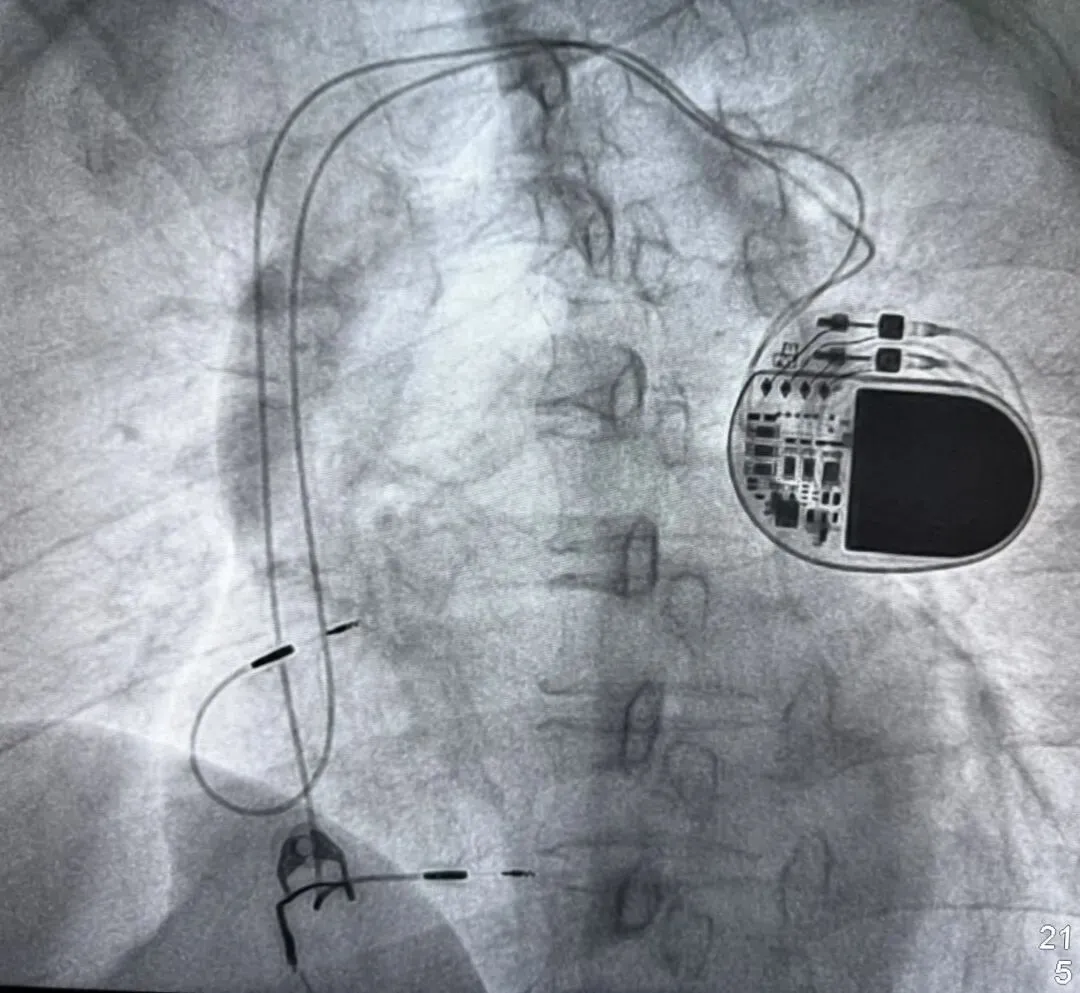

- 唯一有效预防:植入 ICD(心脏除颤器)(针对高危患者)。

注: 评估高危或者有发作史的需要植入心脏起搏器ICD,是预防猝死的关键!

【心脏起搏器程控笔记】几例 ICD 起搏器 ATP 及 Shock 治疗心电图及程控,治疗都合适吗?